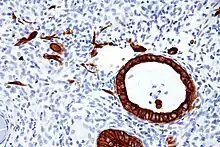

Keratin intermediate filaments in epithelial cells (red stain).